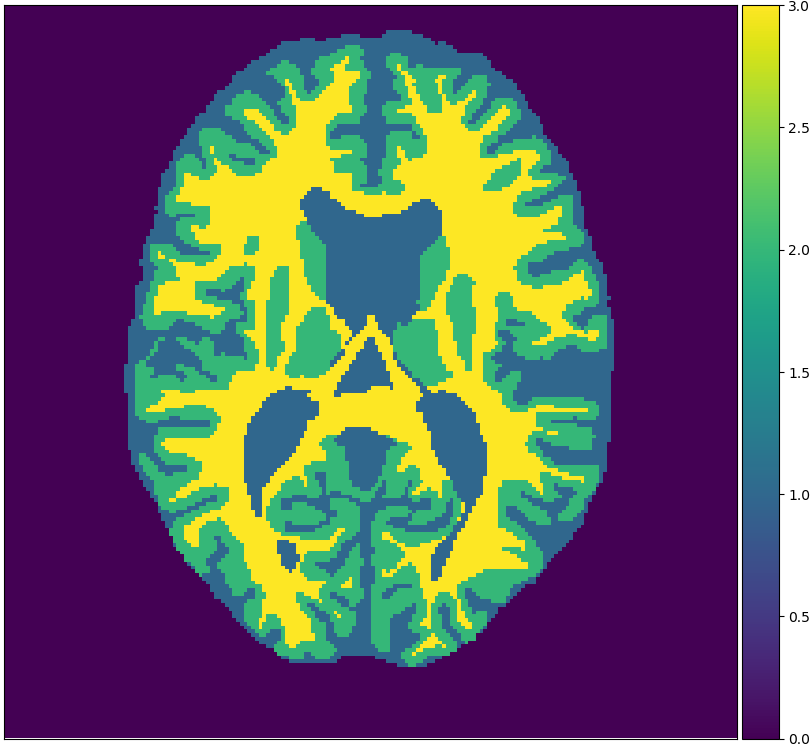

We will make use of 3 publicly available data sets: Brainweb1.5T, MRBrainS13, and IBSR. Each data set originates from one medical center. Brainweb1.5T is based on 20 realistic phantoms from Brainweb [2] and an MRI simulator (SIMRI; [3]). The simulator was set to use TE, TR and flip angle parameters of the 1.5T scanner in the Rotterdam Scan Study [9]. MRBrainS13 is a grand challenge for medical image tissue segmentation methods containing 5 scans for training [14]. The scans are 3T and have been fully manually annotated. IBSR is a classical data set of 18 patients and is automatically segmented but manually corrected [18]. Skulls are stripped off in all scans. Figure 1 visualizes examples from these sets.

Figure 2 shows examples of each segmentation method on the MRBrainS13 data set, with Brainweb1.5T as the source center. For the unsupervised models we only show boundaries between clusters, to indicate that interpretation remains a necessary step. A couple of observations can be made: firstly, the hidden Potts models produce smoother segmentations. Secondly, the U-net over-predicts white matter in the whole image. Thirdly, the 1-nearest-neighbours classifier over-predicts background voxels in fluid regions. Lastly, all methods favour white matter over gray matter in ambiguous regions.